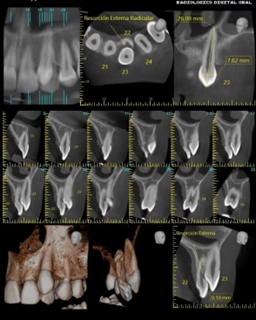

Supernumerario - Reabsorción Radicular

En el caso de un diente supernumerario, es esencial conocer su ubicación precisa y su relación con otras estructuras dentales…